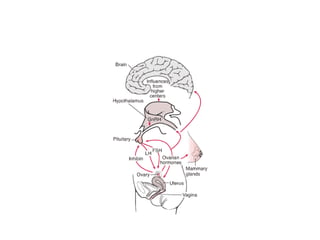

Ovulatory dysfunction

●Alteration in neuroendocrine function

●Continuous estradiol production without corpus

luteum formation and progesterone production

thus causing excessive proliferation of

endometrium lead to necrosis

●Anovulatory bleeding commons in early years

after menarche due to immaturity of HPO axis

and perimenopausal woman due to lack of

synchronization of HPO

●Anovulation causes by

●Extremes of reproductive life

●PCOS

●Hypothalamic dysfunction

●Abnormalities of other hormones(thyroid, prolactin,

and cortisol)

Ovulatory dysfunction ●Alteration inneuroendocrine function ●Continuous estradiol production without corpus luteum formation and progesterone production thus causing excessive proliferation of endometrium lead to necrosis ●Anovulatory bleeding commons in early years after menarche due to immaturity of HPO axis and perimenopausal woman due to lack of synchronization of HPO

• 31.

●Anovulation causes by ●Extremesof reproductive life ●PCOS ●Hypothalamic dysfunction ●Abnormalities of other hormones(thyroid, prolactin, and cortisol)